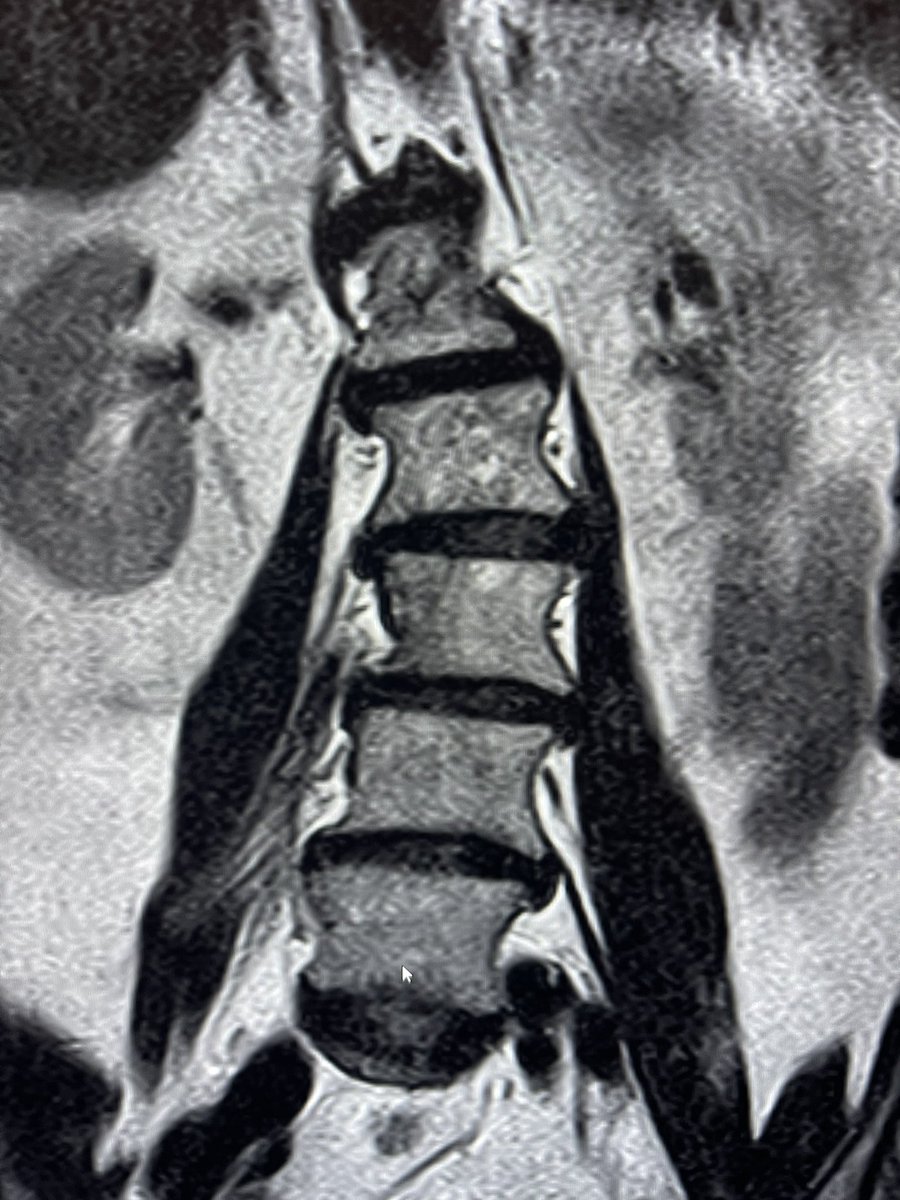

So, this is some real talk regarding #MSKIR in the real world.

@TheStrykerIVS makes a great product, #SpineJack, that shows up in a lot of cool posts on this and other platforms.

This example was just posted by @neuroradiology - a great example of the genre.